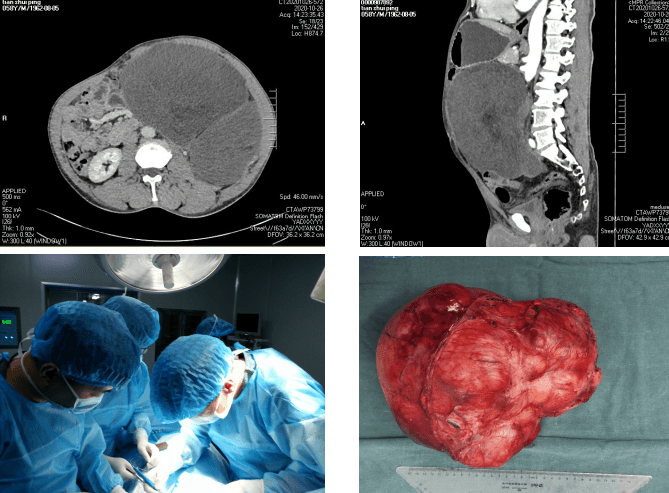

在我院開展醫(yī)療服務(wù)品牌建設(shè)、全面提升醫(yī)療質(zhì)量與醫(yī)療技術(shù)活動(dòng)之際,我院腫瘤/胸外科在苗滿園主任帶領(lǐng)下為一位腹膜后腫瘤患者成功切除了直徑達(dá)35cm的巨大腫瘤,腫瘤比成人頭顱都大,患者目前已順利康復(fù)出院,醫(yī)療技術(shù)及服務(wù)感受度,均受到患者及家屬的一致好評(píng),并收到感謝信一封,錦旗一面。

田某,男,50歲,因“腹脹6月余”入院。查體見腫瘤占據(jù)整個(gè)腹部,經(jīng)影像學(xué)檢查,顯示腹部見一巨大軟組織腫塊影。苗主任對(duì)老人的身體進(jìn)行仔細(xì)評(píng)估,術(shù)前檢查完善后,科室反復(fù)討論后,組織MDT多學(xué)科會(huì)診決定實(shí)施手術(shù)切除,并制定了詳細(xì)的手術(shù)方案及圍手術(shù)期應(yīng)急預(yù)案。2020年5月22日上午,由苗滿園教授、李仁拴主治醫(yī)師等組成的手術(shù)團(tuán)隊(duì)在全麻下為患者行“腹膜后巨大腫瘤切除術(shù)”。術(shù)中發(fā)現(xiàn)腫瘤位于腹膜后,約35cm×30cm×30cm,不規(guī)則型,實(shí)質(zhì)性,占據(jù)左側(cè)腹腔空間,將腹腔內(nèi)腸管等推擠至腹腔右側(cè),左腎被擠壓至右上腹,右側(cè)輸尿管擴(kuò)張。術(shù)中仔細(xì)分離,保護(hù)好腸系膜血管、腹主動(dòng)脈、胰腺、脾臟、結(jié)腸等重要器官,在手術(shù)室的密切配合下,手術(shù)歷時(shí)3小時(shí)完成,切除腫瘤重達(dá)10kg。圍手術(shù)期嚴(yán)格執(zhí)行ERAS流程,給予早期恢復(fù)飲食、術(shù)后第一天即可下床活動(dòng)、多模式鎮(zhèn)痛等一系列治療措施,患者恢復(fù)順利,于術(shù)后10天治愈出院。術(shù)后病理提示腹膜后高分化脂肪肉瘤。

腹膜后腫瘤早期癥狀隱匿,常在生長(zhǎng)至較大時(shí)出現(xiàn)癥狀被發(fā)現(xiàn),但此時(shí)腫瘤常累及大血管、消化系統(tǒng)、泌尿生殖系統(tǒng)等重要臟器,腹膜后腫瘤手術(shù)平均出血約2000ml,止血困難,易導(dǎo)致出血死亡,手術(shù)切除難度極大。本次手術(shù)亮點(diǎn):1. 術(shù)前多學(xué)科MDT、充分術(shù)前準(zhǔn)備,將手術(shù)風(fēng)險(xiǎn)盡可能降至最低;2. 精湛的手術(shù)技巧幫助闖過手術(shù)關(guān):術(shù)中精細(xì)解剖,避免損傷周圍臟器,完整切除了腹膜后巨大腫瘤;3. 個(gè)體化精準(zhǔn)治療讓患者最大程度獲益。